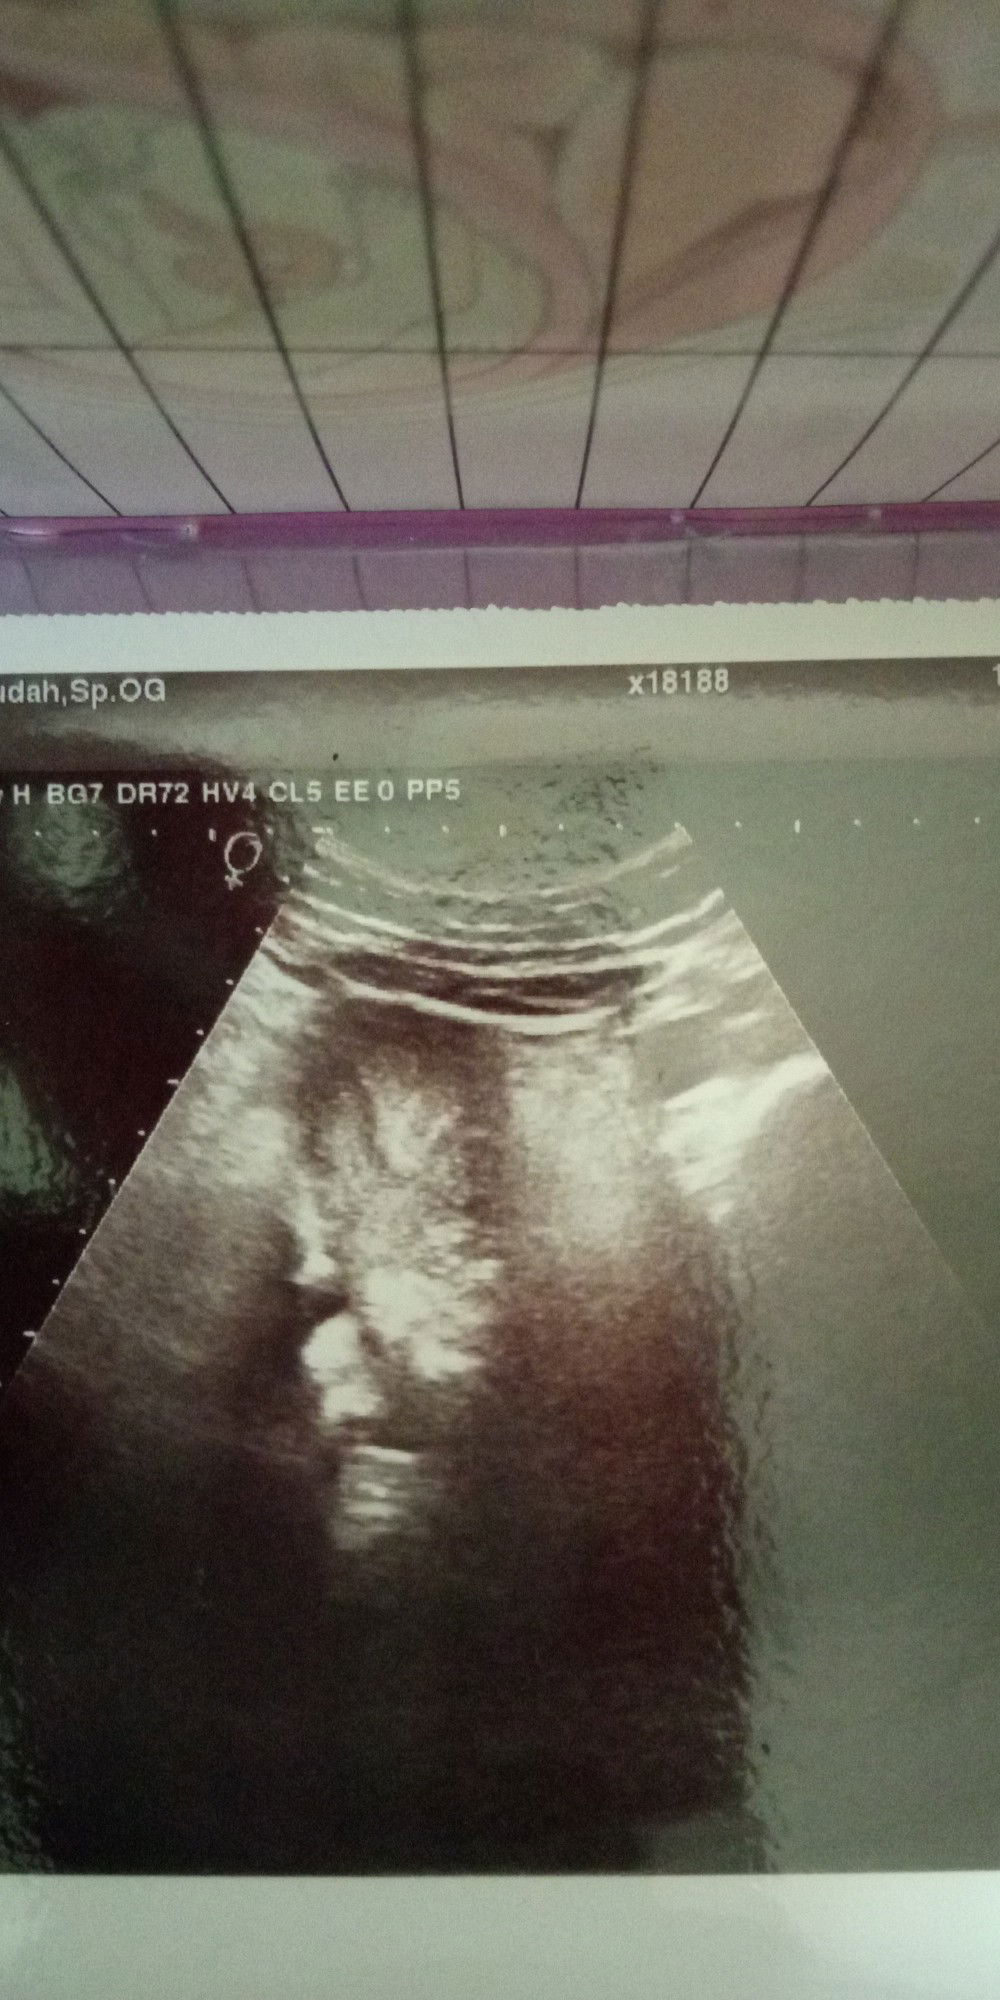

USG Kehamilan Pertama

Bun ak kemarin USG usia kehamilan 5 minggu tpi kata dokternya gk ada kantong janinnya masih pembesaran rahim apa bunda" Juga pernah kyk gni soalnya saya bingung bun ?